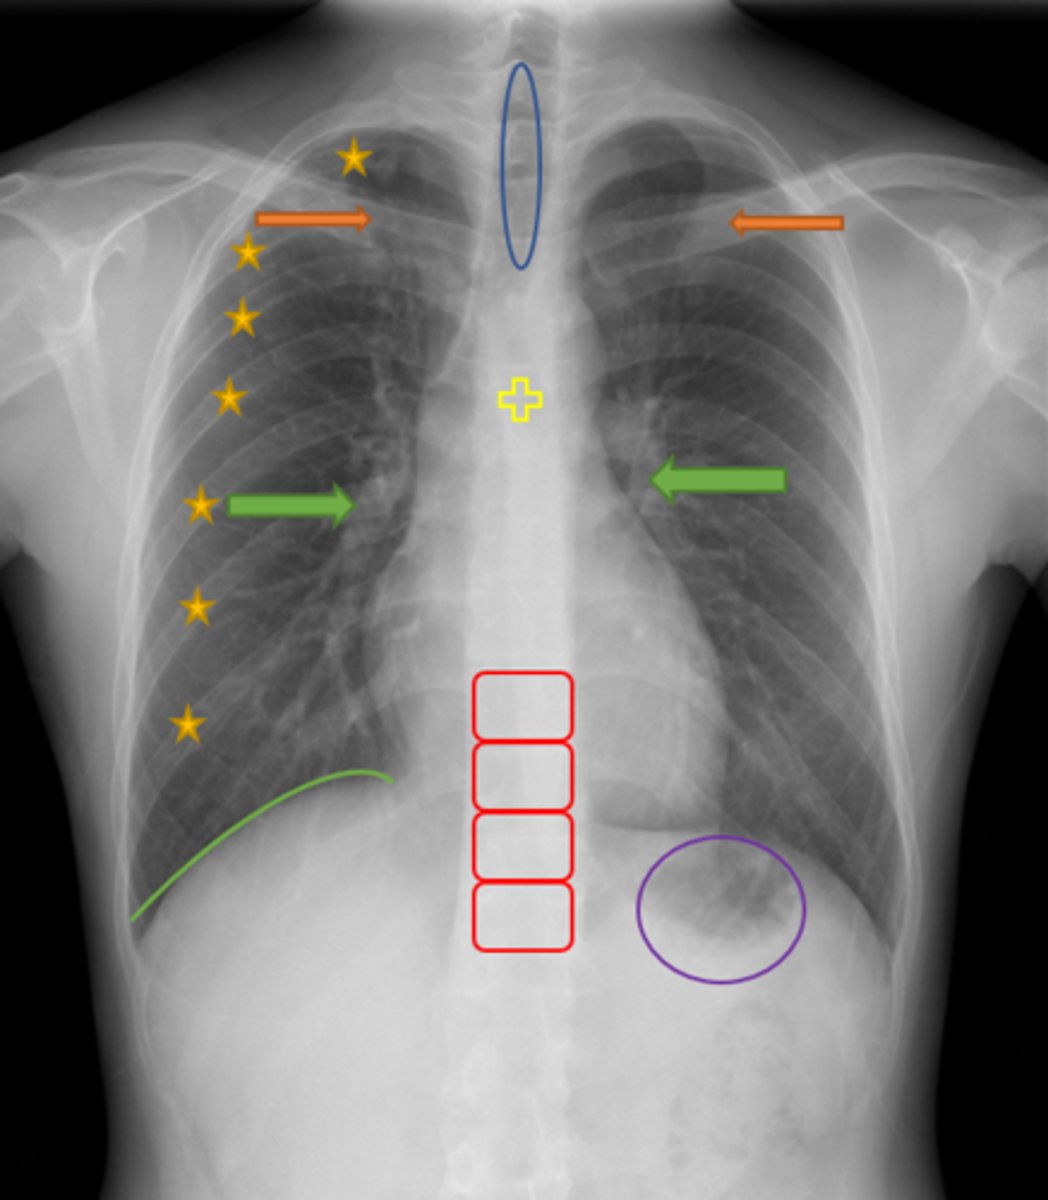

Aortic knob/arch

Pink Arrow

Left ventricle and border of the heart

Purple Line

Pulmonary arteries

Blue Arrows

Normal film

Interpretation

Trachea

Blue Oval

Pulmonary arteries

Green Arrows

Vertebrae/spine

Red Blocks

Clavicle

Orange Arrows

Ribs

Yellow Stars

Diaphragm

Green Line

Gastric bubble/stomach

Purple Circle

Carina

Yellow Cross